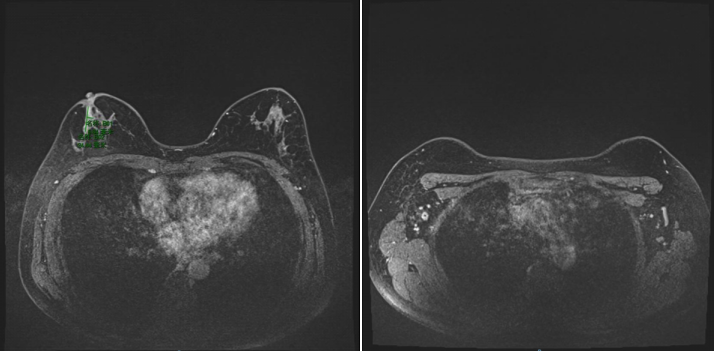

2021-12-01,乳腺MR:右乳外上象限腺体内(约9-12点钟方向,前中带区)见一异常信号肿块影,大小约3.9×2.7cm,符合乳腺癌表现(BI-RADS 6类),侵及邻近皮肤及乳头。右侧腋窝数个增大及稍大淋巴结,较大者大小约为2.1×1.3cm,考虑转移。

图2.乳腺MR(2021-12-01)

2022-4-19,乳腺MR:右乳外上象限腺体内(约9-12点钟方向,前中带区)条片影,大小约2.5×0.7cm,较前明显缩小、强化减低。右侧腋窝数个小淋巴结,较大者短径约0.5cm,较前缩小。

图5.乳腺MR(2022-4-19)